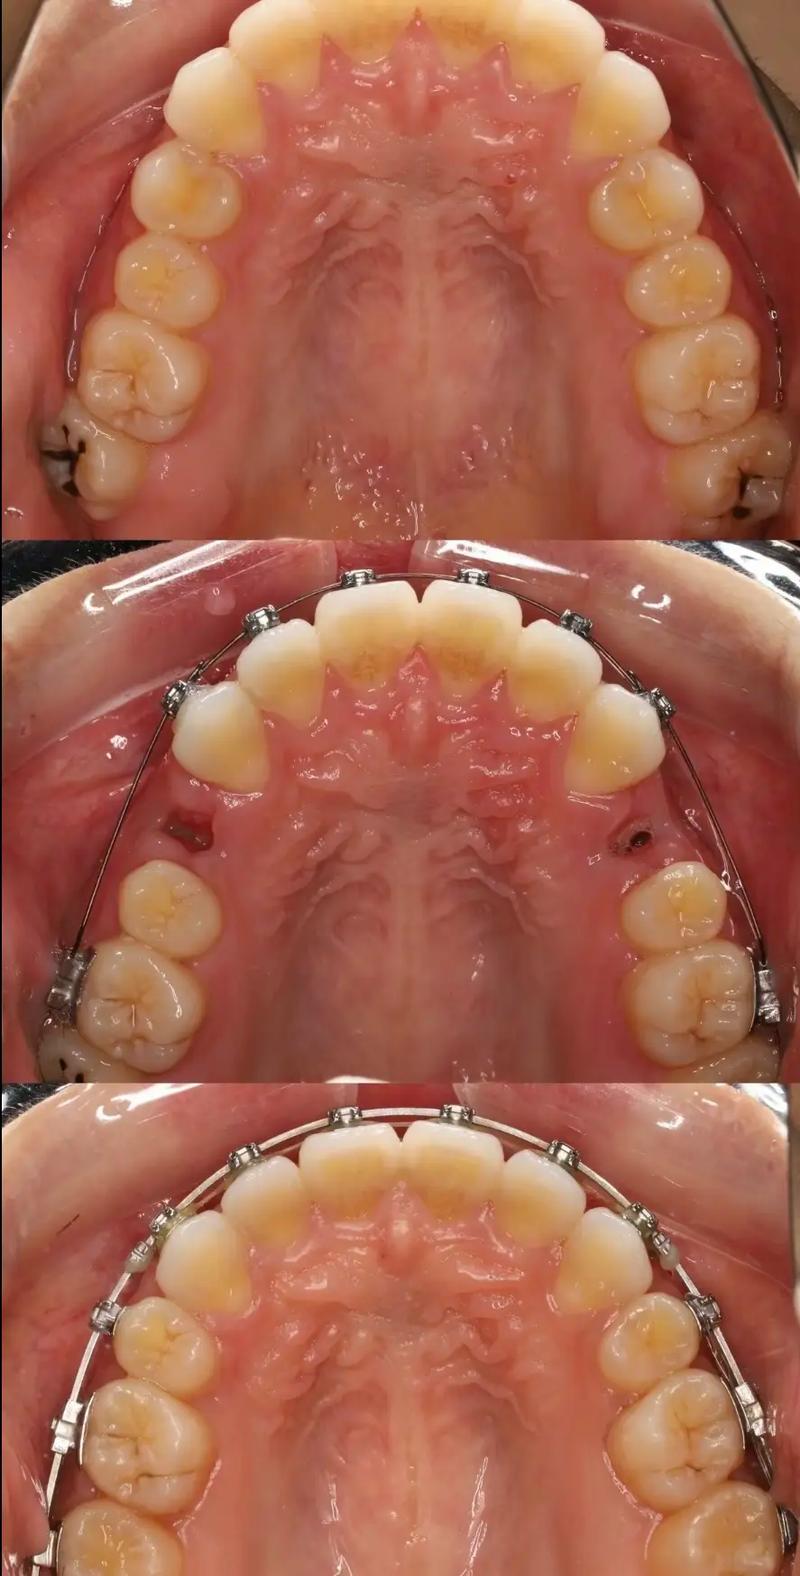

- 片段化:将传统全口弓丝拆分为独立或连接的片段,每个片段对应1-3颗目标牙齿,针对上颌前牙拥挤的片段弓,可能仅包含中切牙、侧切牙的托槽连接段,而磨牙区域保持独立,避免力量传导至非目标区域。

- 精准化:根据牙齿移动需求(如压低、伸长、扭转、内收/外展等),定制弓丝的形态、材质和尺寸,需压低单颗前牙时,片段弓可设计为“L形”,利用杠杆原理将力量集中在牙冠;需纠正扭转时,则通过弯制“转矩”角度,实现牙根的三维控制。

- 诊断与设计:通过口腔检查、X线片(如曲面断层片、头颅侧位片)、模型分析,明确目标牙齿的移动方向和幅度,设计片段弓的形态、材质(如不锈钢丝的强度高、镍钛丝的柔韧性好)和托槽位置(通常选用方丝弓托槽或直丝弓托槽,便于精细控制)。

- 弓丝弯制与试戴:根据设计图弯制片段弓,临床试戴时检查弓丝与托槽的贴合度,确保力量能准确传递至目标牙齿,纠正前牙拥挤时,弓丝需预成“理想弓形”,通过回弹力推动牙齿向牙槽骨中央移动。

- 粘接与加力:将托槽精准粘接于目标牙齿,片段弓入槽后通过结扎丝固定,首次加力力度控制在50-100g(轻力原则),避免牙齿过度受力导致牙根吸收或疼痛。

- 复诊调整:每4-6周复诊一次,检查牙齿移动进度,调整弓丝形态或更换更粗的弓丝(如从0.014英寸镍钛丝换为0.018英寸不锈钢丝),逐步增强力量直至目标达成。